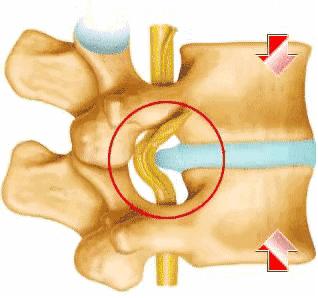

术前CT检查:L5/S1椎间盘突出,黄韧带肥厚。

腰椎间盘突出症是脊柱神经外科的常见病,也是最易被误诊误治的疾病之一,是因腰椎间盘退变、纤维环破裂、髓核突出而刺激或压迫脊神经根、马尾神经所表现的一种临床综合征。